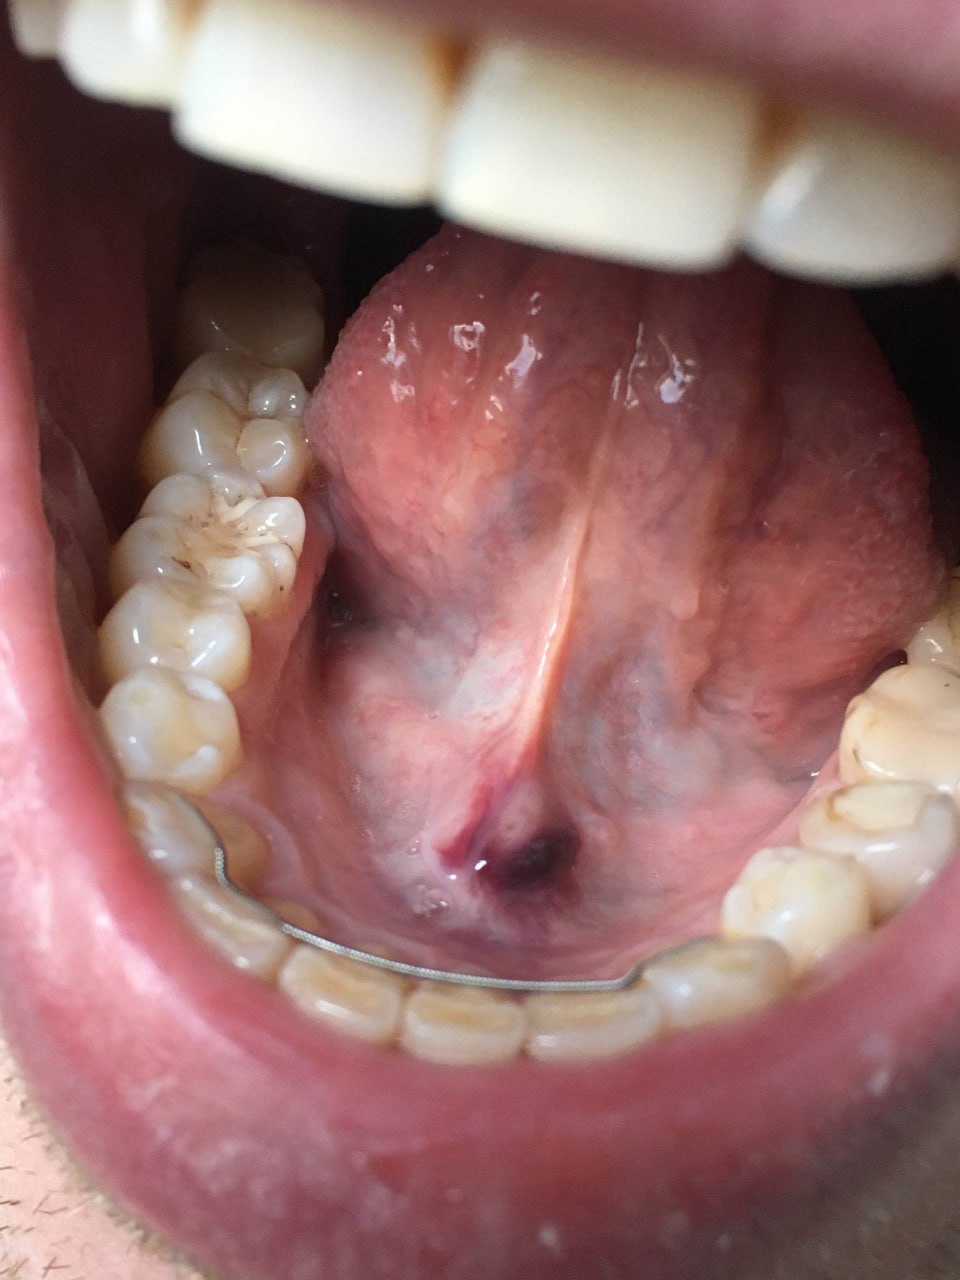

На 8й день после начала приёма фуллерена масла под язык, вот такая штука под языком образовалась. (дозировка по 10-15 капель в день) Было у кого-нибудь подобное?